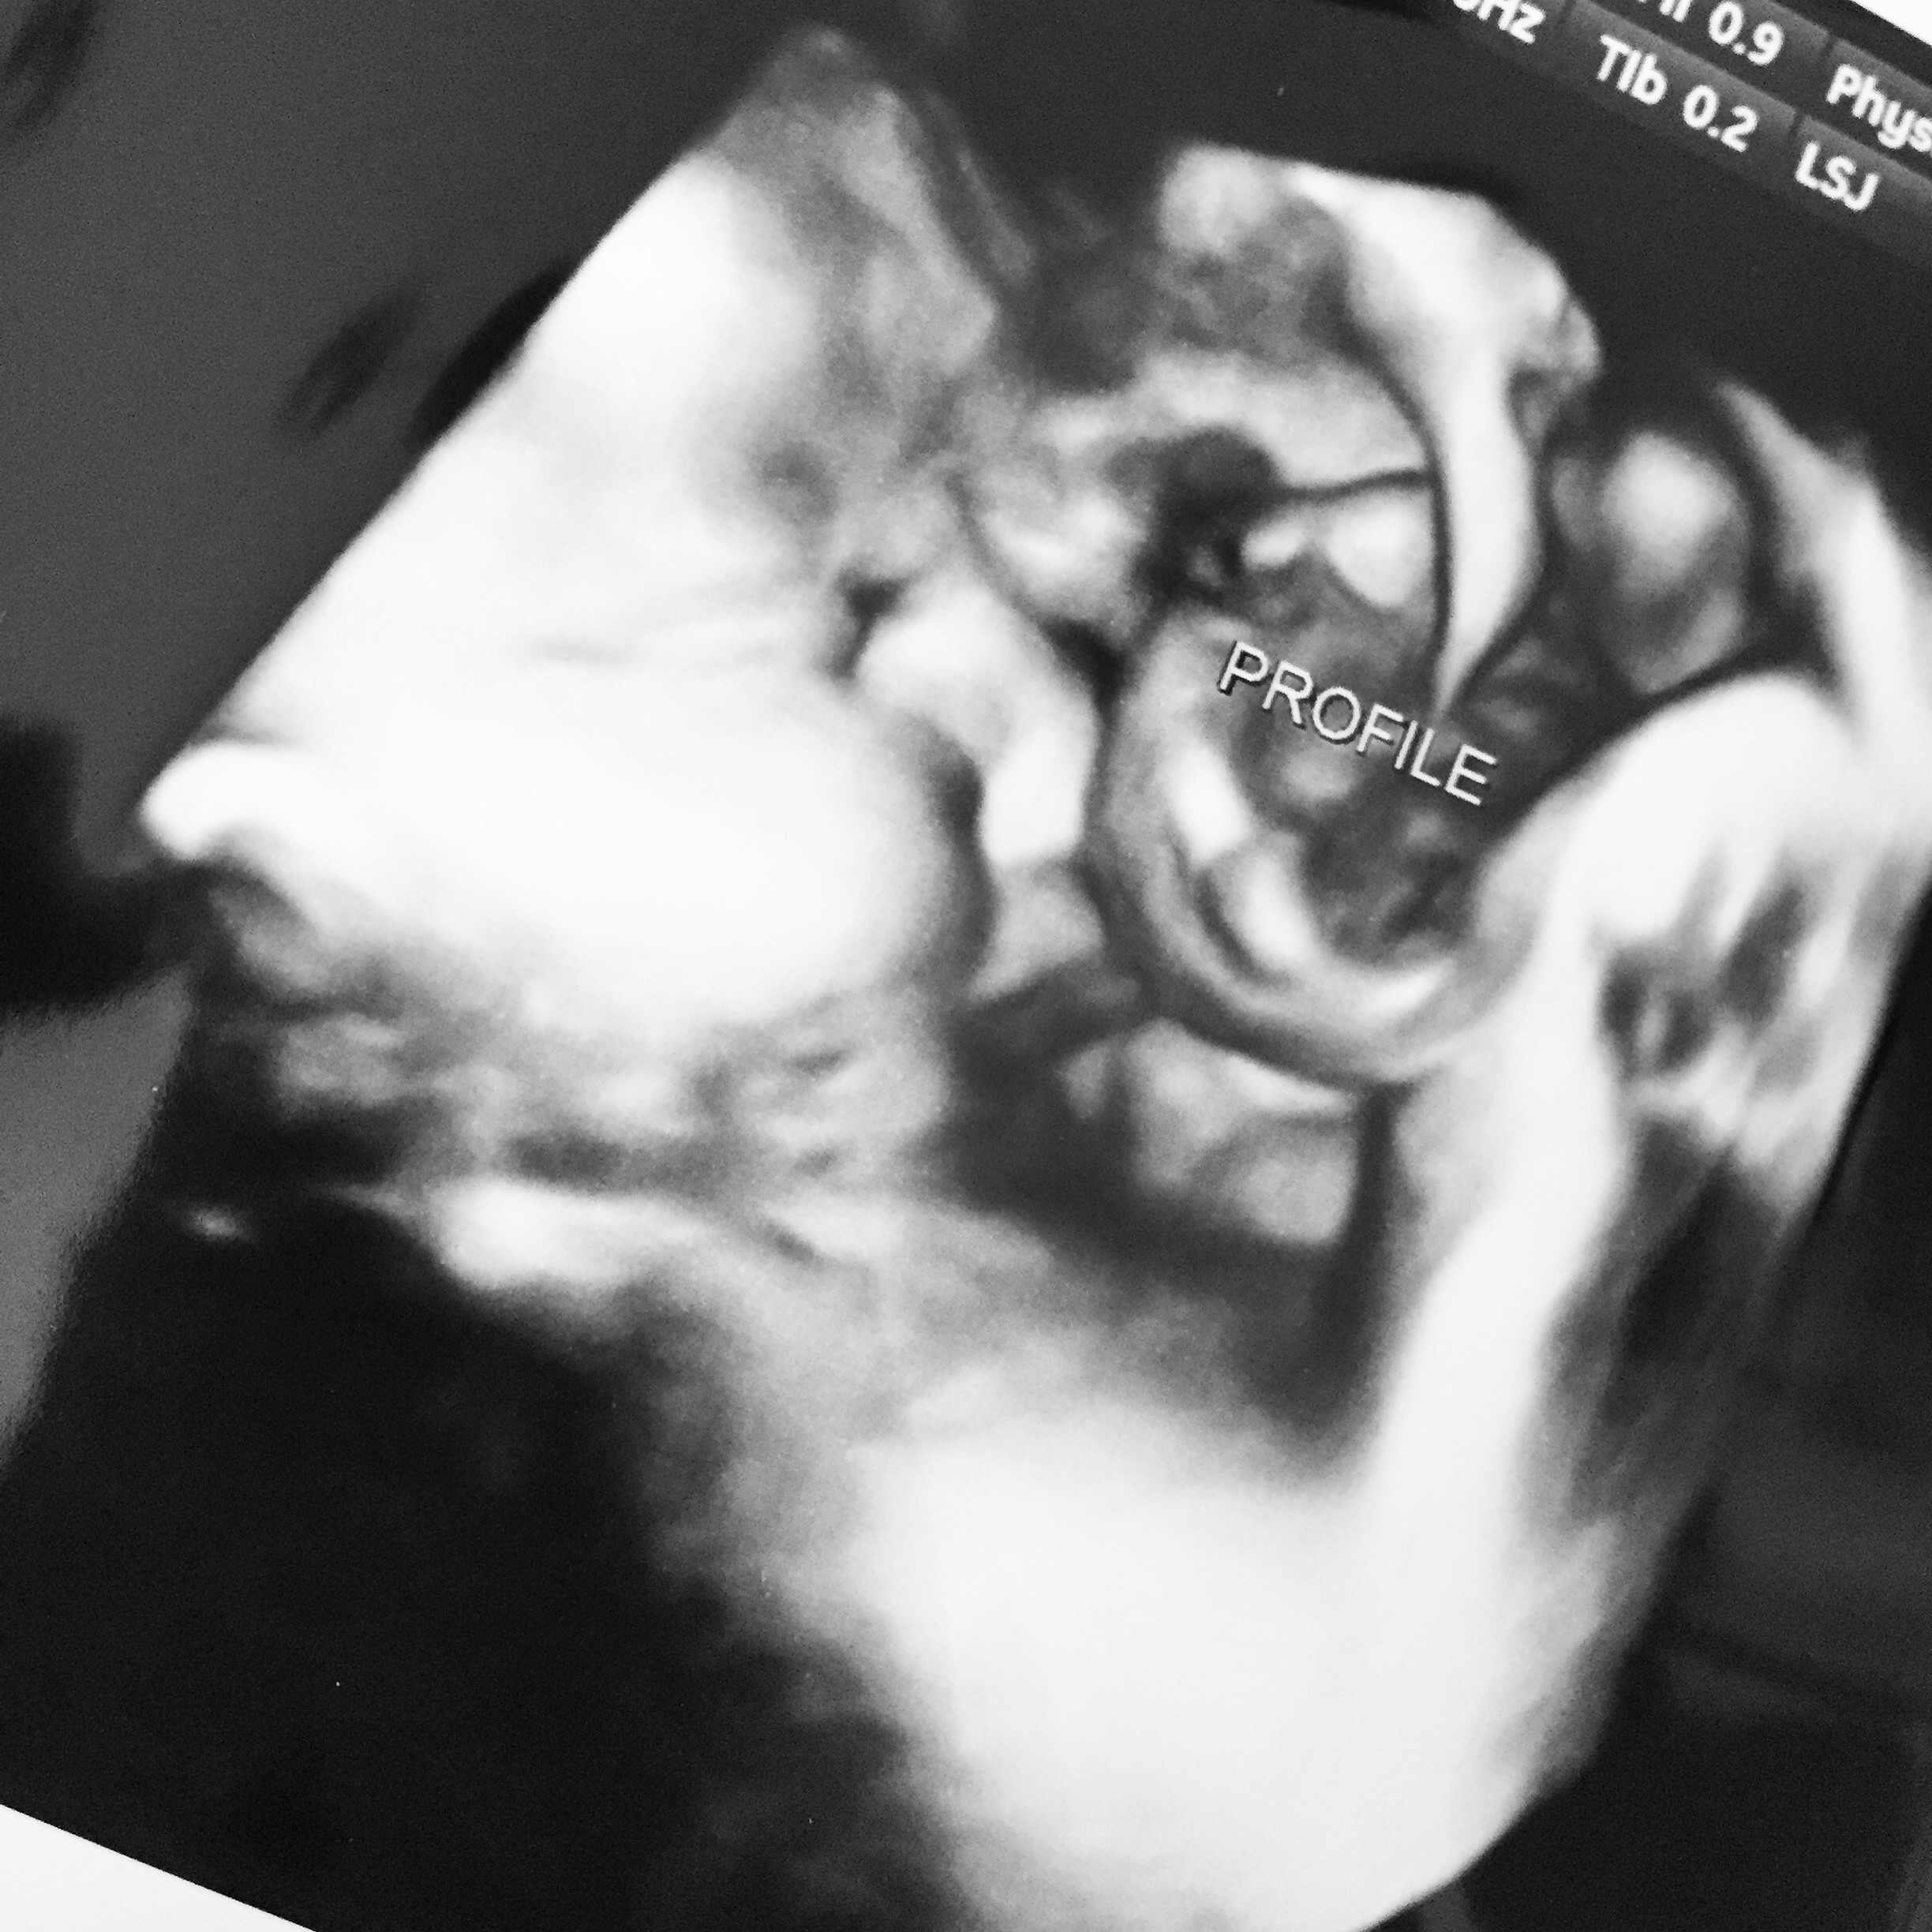

• We waited a little too long to do ours (was 32 weeks). My doctors office says after about 30 weeks they start getting squished in the womb and it's harder to get good pictures. We tried anyway and baby girl would NOT cooperate! She would have her hand over her face or she'd turn her head away, so the pictures didn't turn out very well. The office only charged us half price for that.

A few days before I had had an ultrasound at my specialists office and they managed to get a good shot of her face. It's not 3D but it's still pretty good. When it was over and the tech helped me sit up, she immediately said "it's your nose she's got!" Lol :)